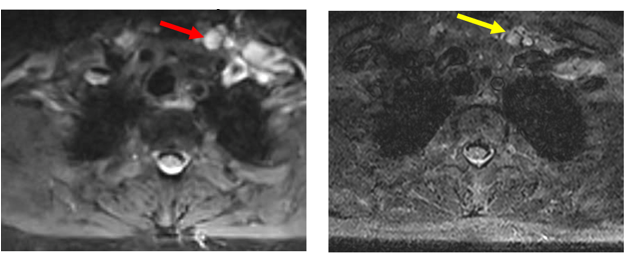

Hình ảnh MRI cổ: Hình ảnh tổn thương vùng hạ họng thanh quản giảm kích thước sau điều trị 3 tháng, từ 41 x 22 mm (mũi tên đỏ) xuống còn kích thước 20 x 13 mm (mũi tên xanh).

Hình ảnh MRI cổ: Hình hạch thượng đòn trái giảm kích thước sau 3 tháng điều trị, từ đường kính 10 mm (mũi tên đỏ) xuống còn 7 mm (mũi tên vàng).